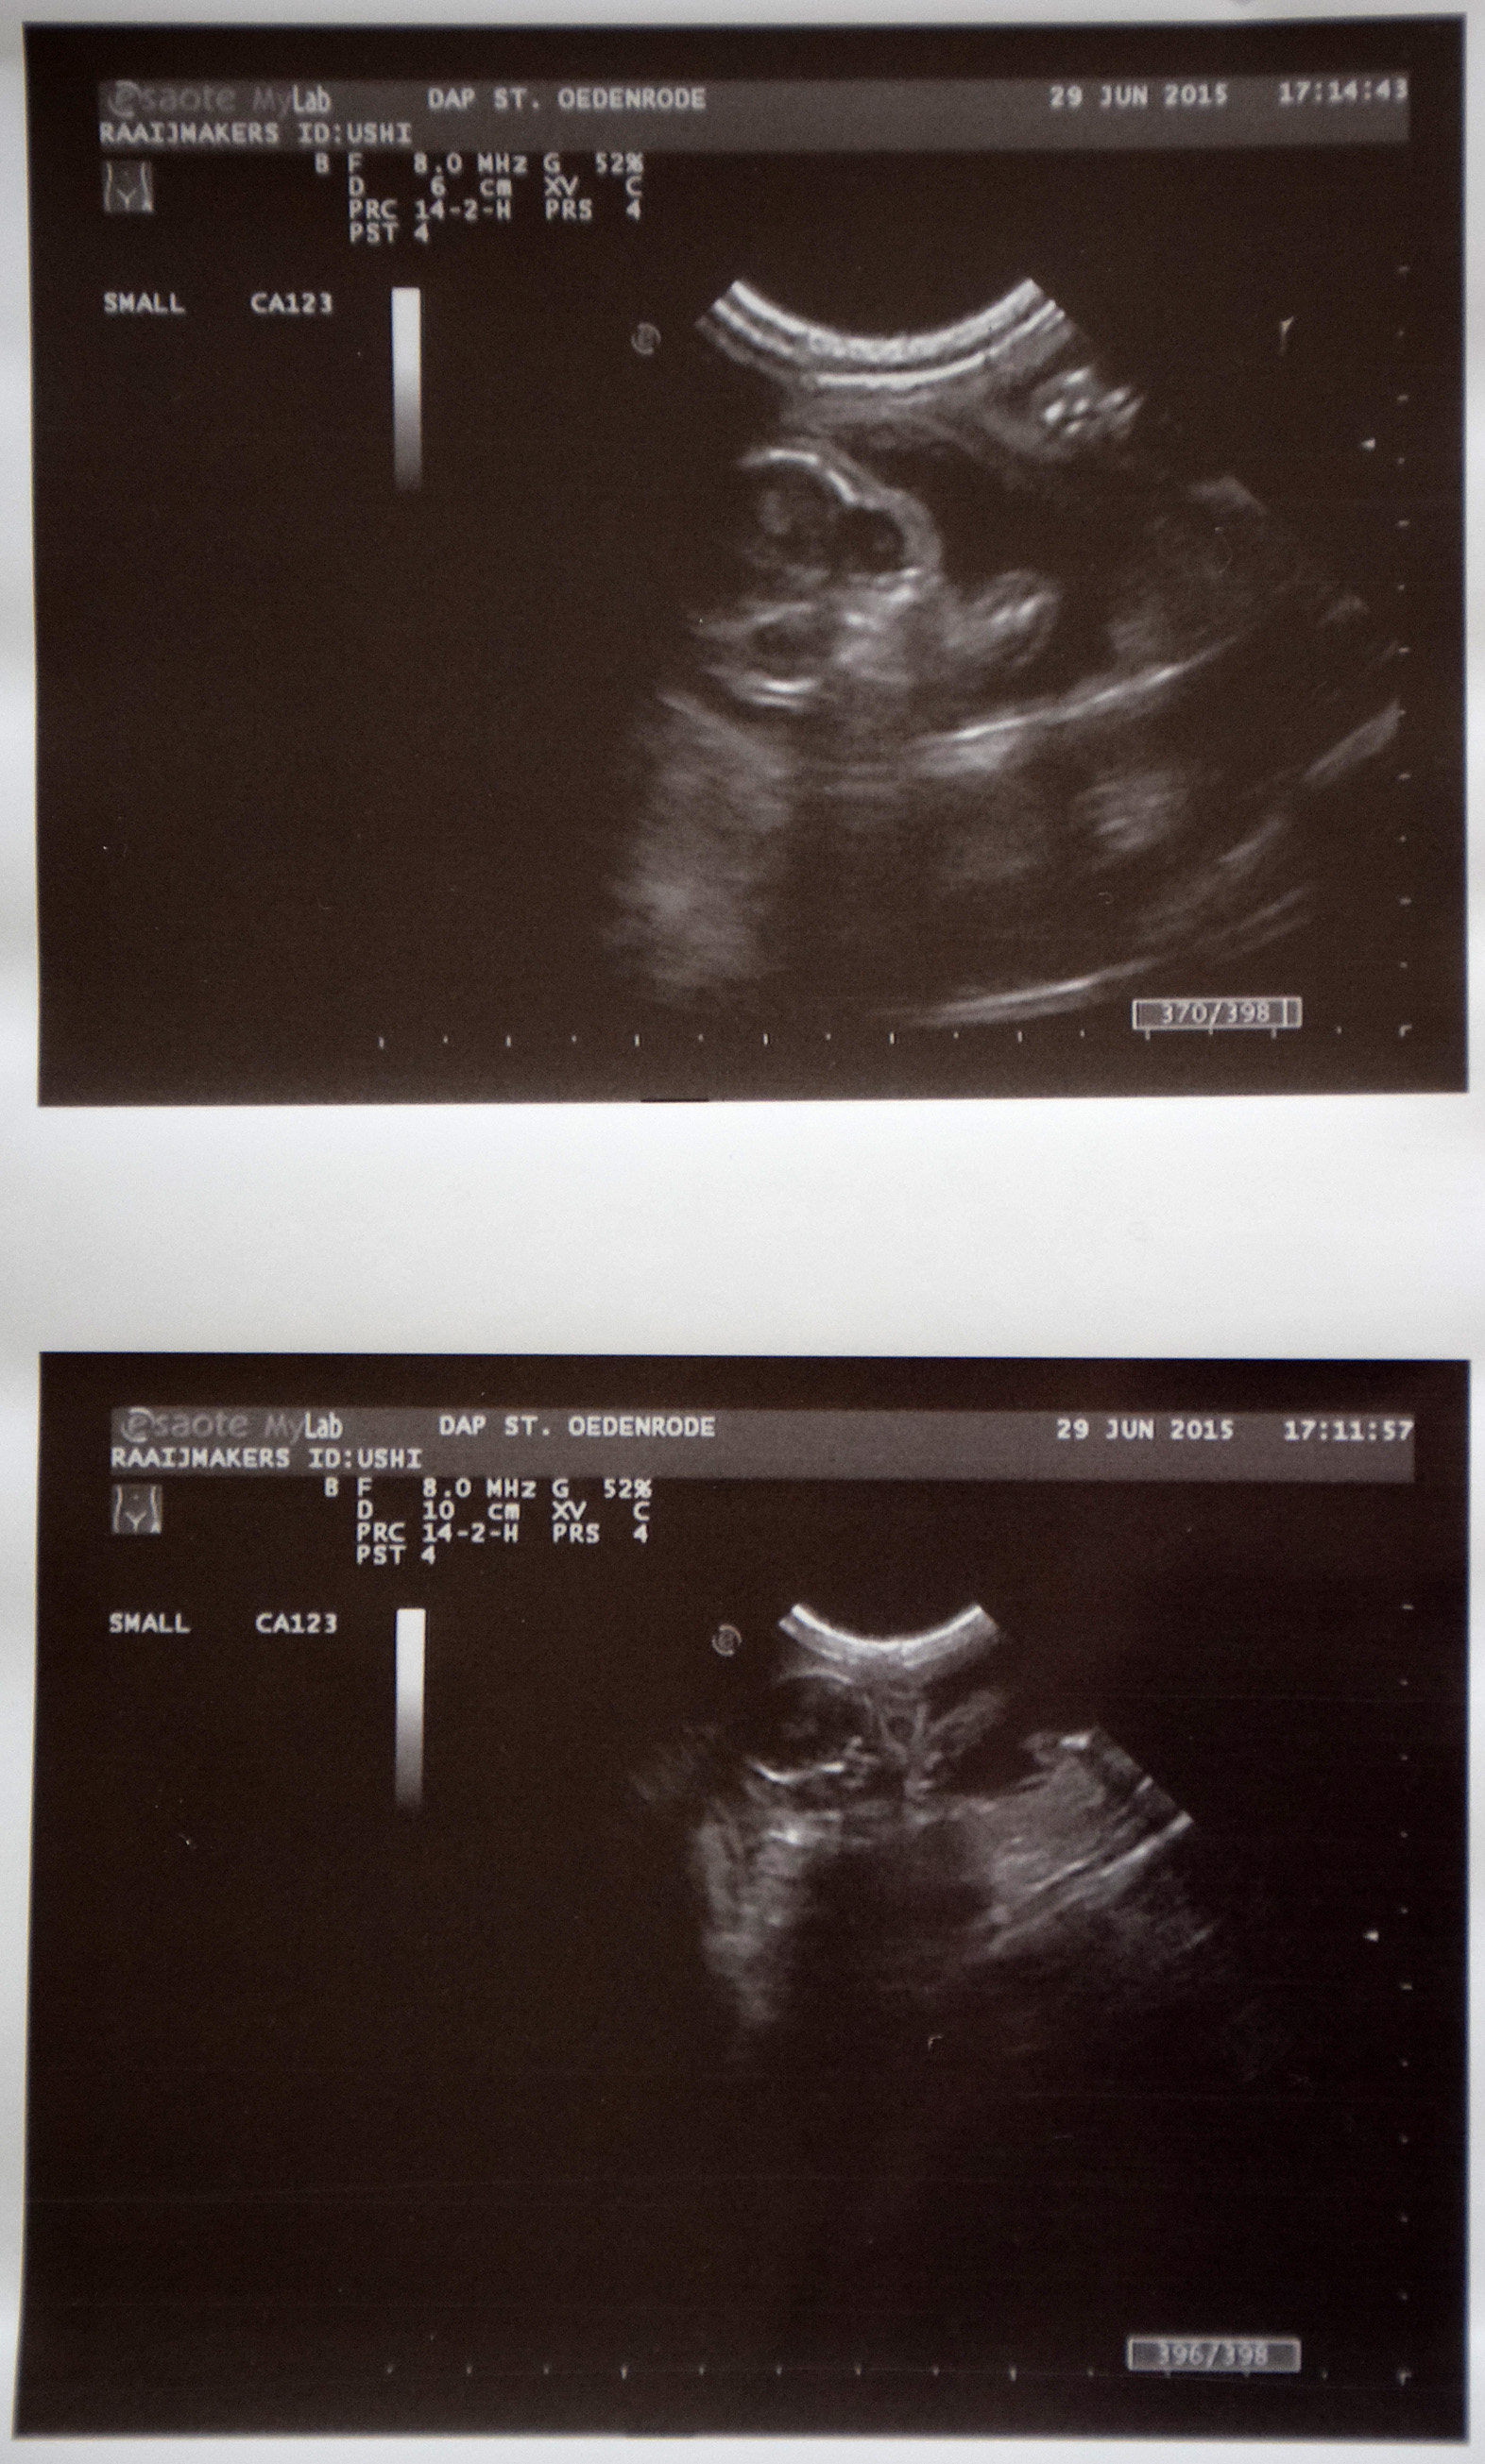

Maandag 29 juni 2015: Zeven weken zwanger

Omdat Ushi nogal wat problemen heeft met haar ontlasting besluiten we toch maar om een echo te laten maken, omdat we zeker willen weten dat de kittens goed groeien.

Nicole, de dierenarts, voert de echo uit, maar waarschuwt ons al dat ze kittens mag tellen. Ushi ondergaat het scheren van haar buikje zonder problemen en al gauw gaat Nicole aan de gang. Al snel komt het eerste kitten in beeld. Oh, wat mooi! Het hartje klopt snel en de grootte van het kitten is ook goed. Vervolgens zien we nummer twee aan Ushi’s rechterkant, maar we tellen niet. Nicole vindt het ook zo mooi dat ze op zoek gaat naar een derde kitten, rechts, maar dat blijkt een niertje te zijn. Tussendoor wordt de blaas ook nog even gecheckt, die ziet er ook goed uit. Aan de linkerkant worden ook nog twee kittens ontdekt. En ja, zelfs Nicole is nu ook actief aan het tellen. Omdat we verder niets zien, maakt Nicole nog een paar mooie foto’s.